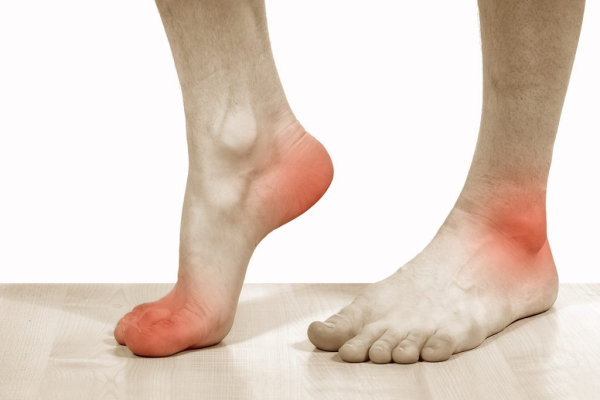

Это редкое доброкачественное хрящевидное образование, поражающее, прежде всего, кости нижних конечностей (чаще верхний конец большеберцовой кости). Может обнаружиться в пяточной и метатарзальной костях, иногда в ребрах, плечевых или тазовых костях. Описаны редкие случаи образований на черепе, грудине и позвоночнике. В детском возрасте характерны мышечная атрофия и местная гипертермия, сильный рост опухоли, болезненность в месте ее локализации, например, боли в области плеча, груди, ноги и т. д.

Околоногтевая

Такая фиброма имеет название опухоль Кенена. Это опухолевидное образование на тканях, окружающих ноготь. Опухоль Кенена наблюдается в подростковом возрасте и чаще всего располагается на пальцах ног, что доставляет неудобство при ходьбе. Основной причиной развития околоногтевого нароста является туберозный склероз.